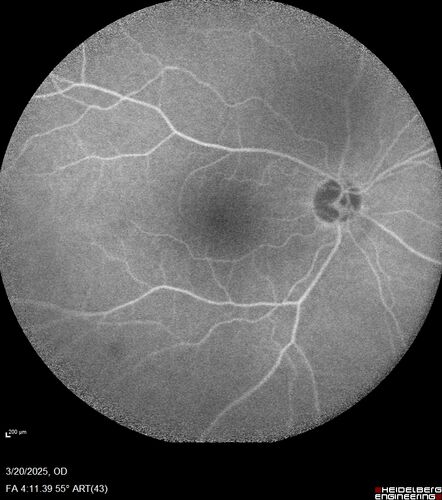

Paclitaxel induced cystoid macular edema - reversed when chemo stopped

74 year old retired physician  About 2-3 weeks ago there was gradual vision loss in the right eye. The patient was seen by an ophthalmologist who saw macular swelling and injected vabysmo. He has been on chemotherapy (Carbiplatin and Carboxytaxol for 2 cancers - advanced prostrate diagnosed 2019 - has had brain surgery AND squamous lung cancers treated with radiation)

Medical Hx: Prostate cancer (Onset: 2018). Pulmonary and bone cancer metastatic. Brain cancer metastasized from prostate cancer.

Surgical Hx: Right frontal & Frontoparietal Craniotomy (Onset: 2024). Appendectomy. Hemorrhoidectomy. Herniorrhaphy. Prostate. Systemic Meds: Chemotherapy. Radiation. Eligard Every 3 Months 22.5 MG per 0.375 ML Prefilled Syringe. MIRALAX prn. Tums Freshers 500 MG Chewable Tablet. Vitamin D. XGEVA.

VA OD: Dcc20/125+1

VA OS: Dcc20/125-2

TP: OD:12 OS:15